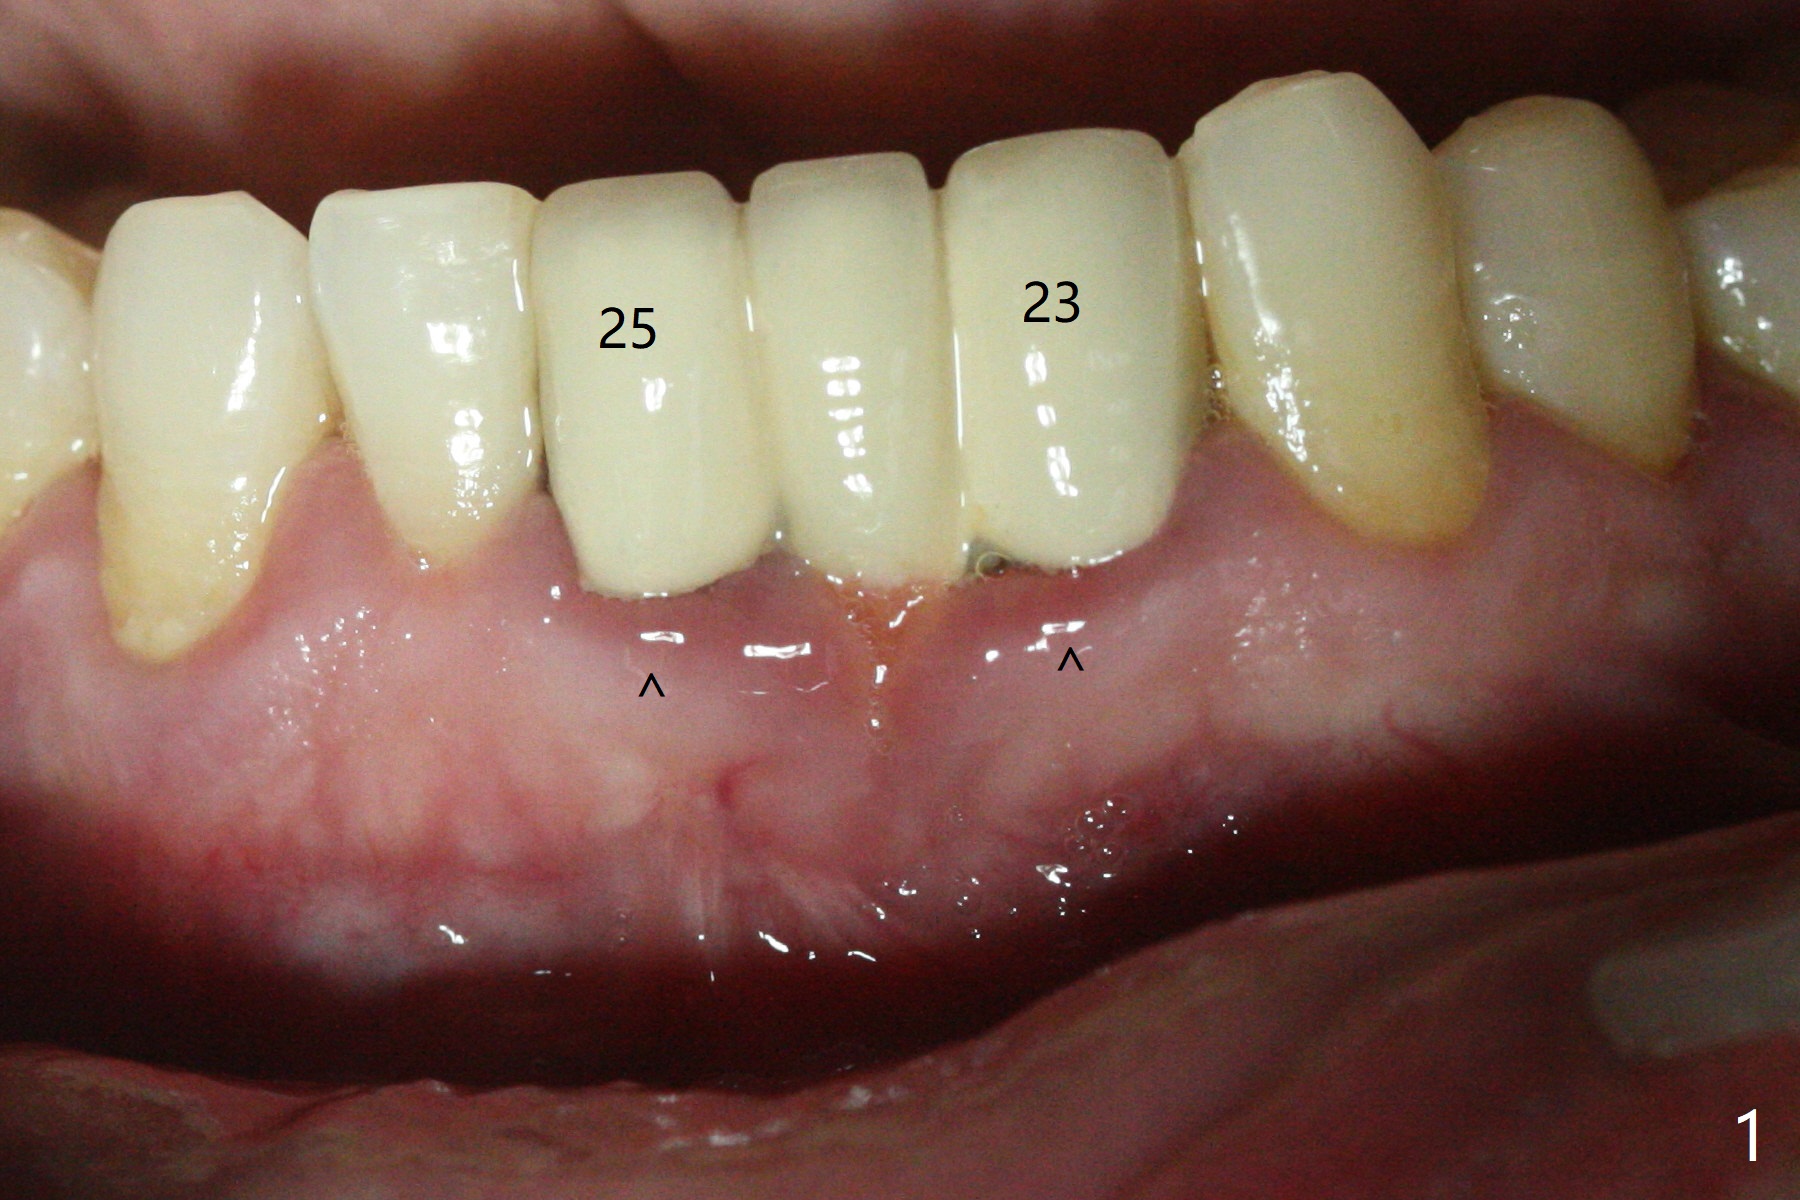

A 38-year-old man has gingival erythema and edema associated with #23-25 bridge (Fig.1). The most abnormal finding is the long pink porcelain at the pontic (Fig.2, 3: P). After taking Alginate for future provisional, the bridge is removed. The edentulous ridge must be atrophic, as shown in low density (Fig.3: *). A 2.0 mm 1-piece implant is proper for the site, as will be shown by CT. In fact 2.5 mm one is proper (Fig.4). The gingival erythema reduces significantly post bridge removal, SRP and water pik. After incision, surgical handpiece and diamond round bur are used to flatten the ridge until 4 mm.